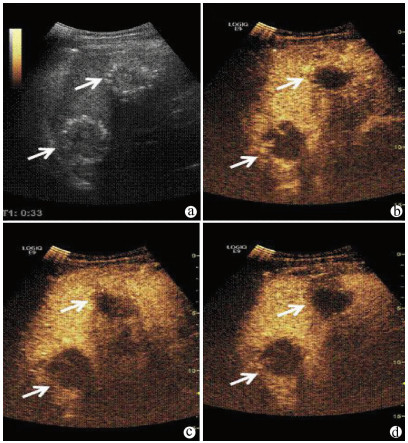

肝病超声诊断指南

中华医学会超声医学分会, 中国研究型医院学会肿瘤介入专业委员会, 国家卫生和健康委员会能力建设和继续教育中心超声医学专家委员会

2021, 37(8): 1770-1785. DOI: 10.3969/j.issn.1001-5256.2021.08.007

超声检查无创、实时、价廉,无辐射、便于反复进行,是最常用的肝脏影像学检查方法。近年来,超声检查新技术如超声造影、弹性成像发展迅速,可有效鉴别肝内占位性病变性质、评估肝纤维化和门静脉高压程度以及监测肝病治疗效果,在临床肝病及其介入治疗中发挥重要诊断价值。本指南规范了肝病多模态超声技术(灰阶超声、彩色多普勒超声、超声造影、弹性超声)检查的仪器调置、患者准备及医生检查方法;对肝脏弥漫性病变(炎性病变、纤维化、硬化)、多种占位性病变及肝病介入操作的多模态超声技术诊断标准进行了定义和规范,同时推荐了超声监测周期及肝脏疾病超声诊断报告书写规范。